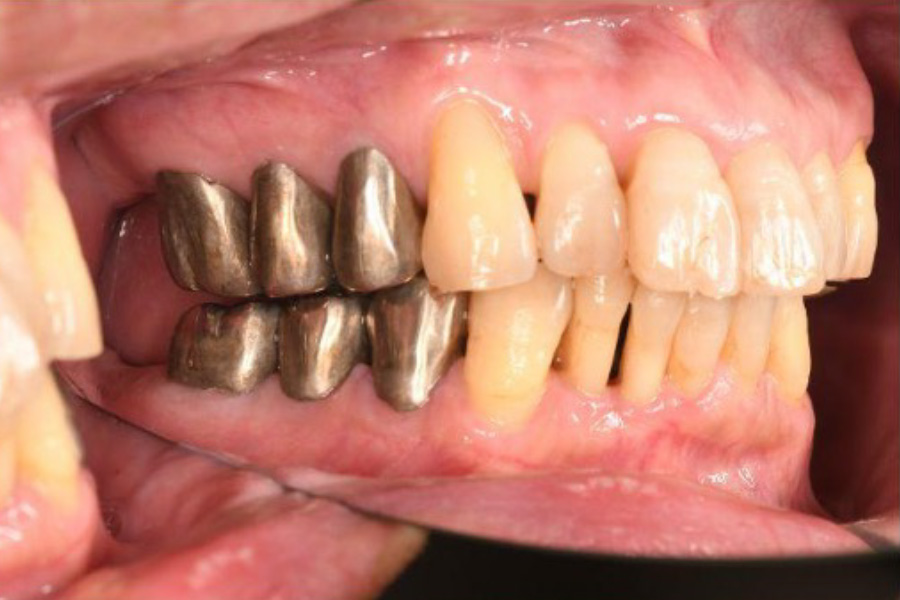

治療前

| 治療内容 | 全顎治療:歯周病治療、抜歯、根管治療、 咬合治療・矯正治療、フルメタルクラウン(保険) |